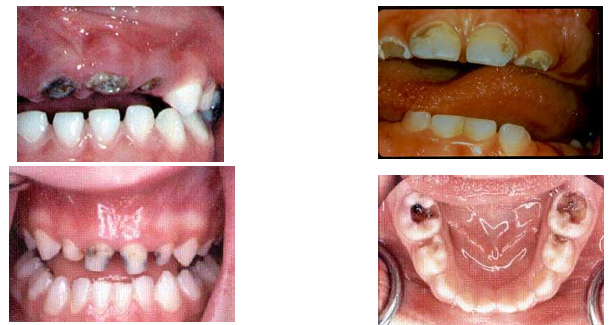

advanced/severe decay

-decay that extends all the way to the gingiva anteriorly or very extensively occlusally in the posterior

sequalae of ECC

-extreme pain

-spread of infection

-difficulty chewing

-poor weight gain

-extensive and costly dental treatment

-risk of dental decay in permanent dentition

-malocclusion

-missed school and work days

-impaired language development

-inability to concentrate in school

-reduced self-esteem

-possible facial cellulitis requiring hospitalization

-possible systemic illness

-death